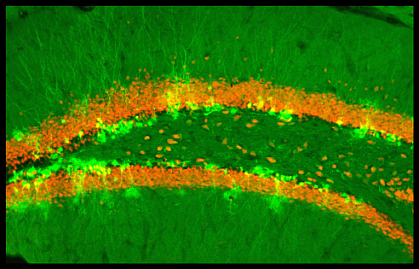

Previous research had shown that blocking the birth of new neurons in a part of the hippocampus, the brain’s memory center, decreased pattern separation ability. Until now, however, scientists had found it difficult to selectively increase the number of young neurons in an adult animal to test whether the opposite held true.

To enhance the survival of newborn neurons in the brain, the team bred mice whose neural stem cells lacked a gene that causes programmed cell death. Compared to mice that still had the gene, these mice were better at distinguishing between a chamber where they had previously received a mild foot shock and a similar-looking chamber that was safe. This showed that more neurons led to greater pattern separation ability.